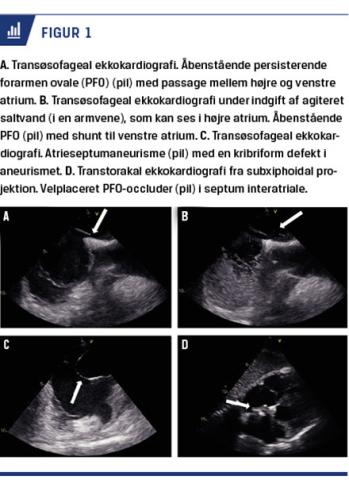

Persisterende foramen ovale (PFO) er en medfødt defekt i septum interatriale og kan ses sammen med et atrieseptumaneurisme (Figur 1) [3]. Prævalensen af PFO er estimeret til 15-25% blandt alle voksne, mens atrieseptumaneurismer kun findes hos 2-3% [4-6]. PFO er tidligere fundet at være associeret med en øget risiko for iskæmisk apopleksi [7]. Da kryptogen apopleksi og PFO også ses hos unge patienter, der har mange resterende leveår og derved risiko for recidiv, har der været stor fokus på at finde den rette sekundære profylakse for denne patientgruppe [8].

Kryptogene apopleksier defineres som opstået uden oplagt årsag. Typiske årsager skal altså udelukkes – herunder bl.a. atrieflimren, kardissektioner og storkarssygdom. Ved PFO forbliver foramen ovale åbent (Figur 1). Passagen tillader perifere emboliers bevægelse fra højre til venstre atrium og efterfølgende videre til det systemiske kredsløb (paradoks emboli) [9]. Hos størstedelen af patienter med PFO (hos nogle kun ved Valsalvas manøvre) vil man kunne påvise en shunt af blod fra højre til venstre atrium [10]. Hos patienter med forhøjede fyldningstryk i venstre ventrikel (f.eks. ældre, patienter med hjertesvigt eller med langvarig hypertension) vil shunten kun sjældent kunne forløbe fra højre til venstre atrium. Paradokse embolier er således lidet sandsynlige i denne patientgruppe (Figur 1) [11]. Shuntning af blod fra højre til venstre atrium kan påvises ved transtorakal eller transøsofageal ekkokardiografi med samtidig indgift af saltvand og Valsalvas manøvre. Størrelsen af shunten vurderes ud fra antallet af bobler i venstre atrium. Større shunter er forbundet med øget risiko for iskæmiske apopleksier [9, 12].